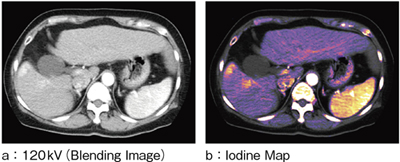

収集したデータは,2種のkV画像として提供可能なほか,ヨード造影剤によるCT値シフト量を表示するIodine MapやIodine差分画像,任意のkV画像を作成するBlending Image,結石の成分を評価するStone Analysisなどの解析ができる。これらの解析に対象部位の制限はなく,あらゆる臓器に対しての解析評価を可能としている(図5)。

図5 Dual Energy(肝細胞がん)